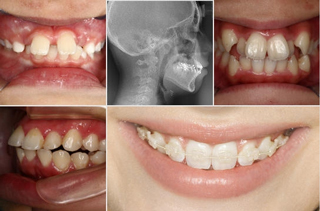

前歯の歯並び悪さは気になるところです。前歯の生え変わりが始まったら早目にご相談ください。矯正装置が目立つのでいやだという方もいらっしゃいますが、当院では透明のブラケットと白くて目立たないワイヤーを使用しています。透明のマウスピースを使用する方法(インビザライン)が適応となる場合もあります。また矯正用ミニスクリューを使用することにより以前にくらべ矯正装置の装着の違和感が非常に少なくなっています。

子どもの場合、矯正治療を開始するのに適した時期は症状によって異なりますが、だいたい永久歯が生え始める6~7歳で矯正治療を始めるのが最適で、治療期間が短くて済むことが多いです。

当院では「7歳までに歯並びと咬み合わせのチェックを!」と呼びかけています。この頃は乳歯から永久歯に生え変わる時期で、顎の成長が旺盛なため、矯正治療において非常に大切な骨格的なバランスを治療できる可能性があるからです。ただ矯正治療は本人自身の協力が不可欠なため、本人が矯正したくなったときが治療に最適な時期とも言えます。

歯並びや咬み合わせについて気になることがあったらいつでもご相談ください。